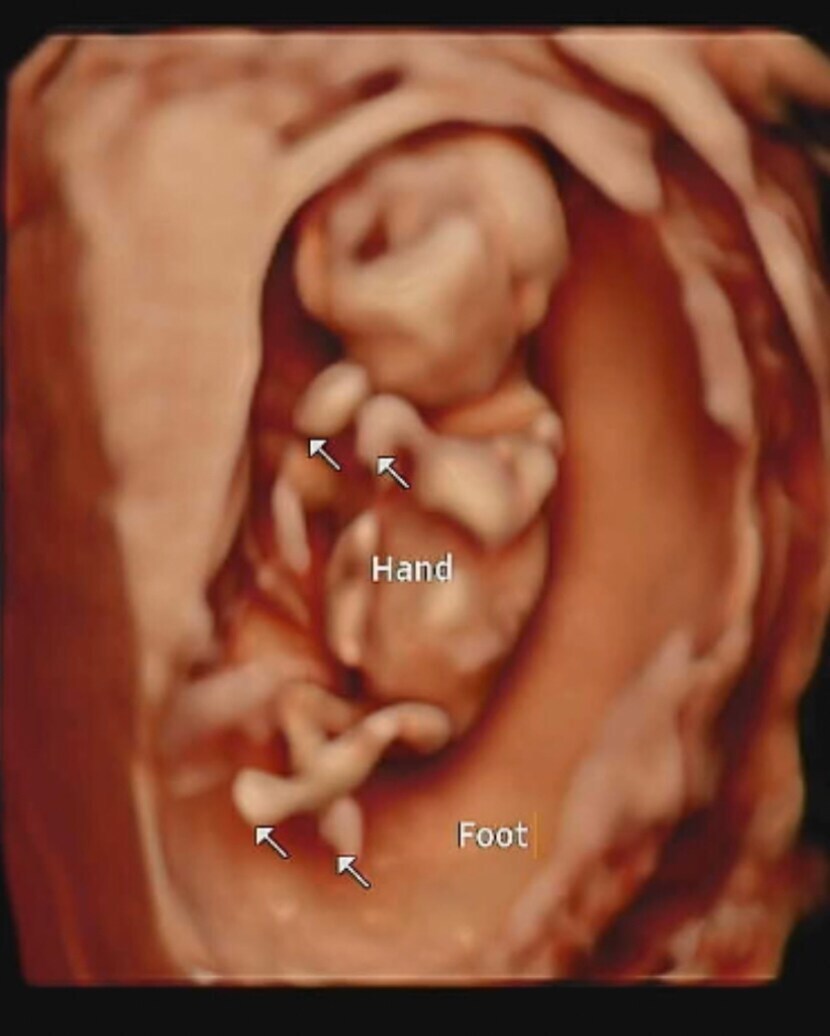

22.12.22 97 읽음 첫 입체초음파❤ 스크럼프 구독하기 0 3 콘텐츠의 수익 2 기다리고 기다리던 병원가는날!1차 기형아검사 하는날이에요 두근두근목덜미 투명대는 정상이래요코도 오똑하고 손발 모두 잘 있어요키는 6센치라네요입체초음파는 처음이라 너무 기대됐어요우리 식빵이 얼굴을 처음 보는날이에요솔직히..다른사람들 입체초음파 보면 약간...외계인같아보였는데..ㅎㅎ우리식빵이는 왜케 이쁜거죠❤??ㅋㅋㅋㅋㅋㅋ 3 0 / 300 입력